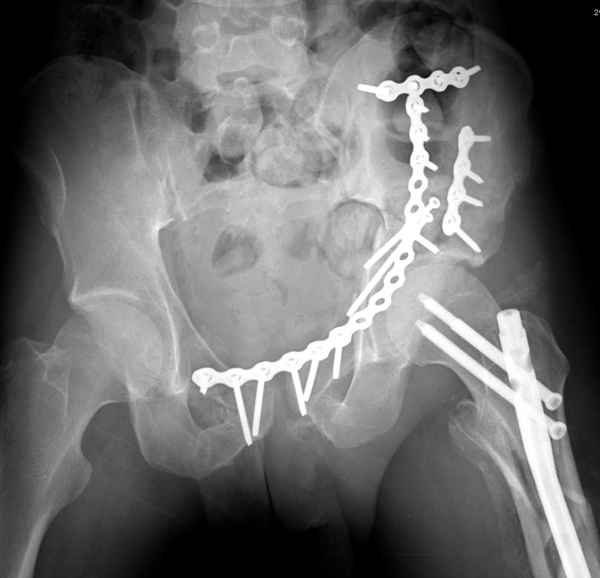

По-моему, надо готовить больного к будущей артропластике, но без опоры на задний столб невозможно удержать протез. Опорная конструкция (кольца и т.д.) должны иметь опору, и поэтому мы бы сделали реостеосинтез задним доступом. При надобности остеотомия и рутинная фиксация с межколонными винтами.

Здесь несколько вариантов двухколонных свежих переломов, которые были оперированы из одного-заднего, а также из двух: переднего и заднего доступов.